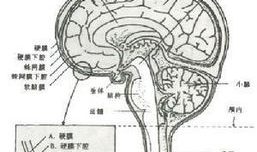

脑膜刺激征检查视频,直观解析临床诊断技巧

你有没有想过,去医院看病的时候,医生有时候会给你来点“特殊待遇”?比如说,给你做个脑膜刺激征检查。这听起来是不是有点陌生?别急,...